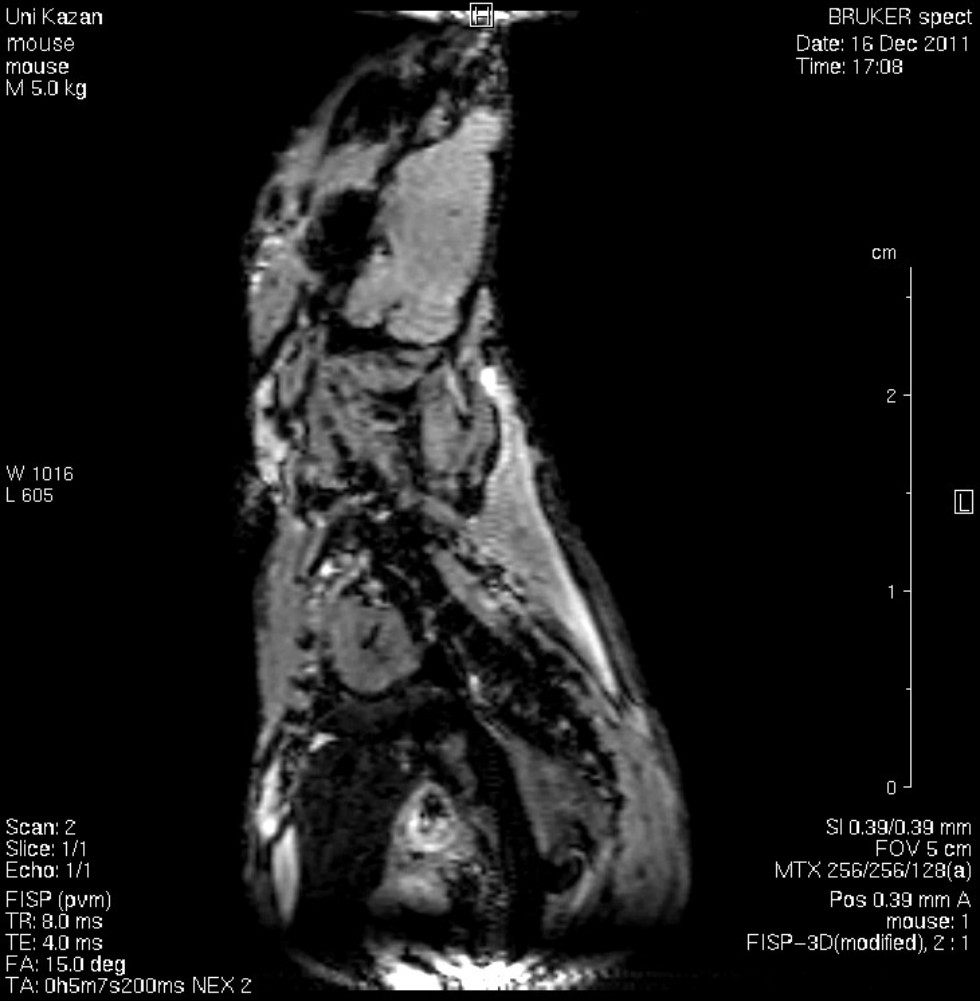

Кафедра физики молекулярных систем ориентирована на развитие методов и разработку приборов магнитного резонанса для решения биологических, медицинских и прикладных задач. Значимость результатов применения методов магнитного резонанса в физике, химии и медицине подтверждается пятью Нобелевскими премиями (1944, 1952, 1991, 2002, 2003 гг). В учебной программе большое внимание уделяется изучению методов магнитно-резонанской томографии (МРТ), компьютерной томографии (КТ), позитронно-эмиссионной томографии (ПЭТ).

Обучение студентов основам физики происходит на современном лабораторном оборудовании. С первых лет обучения студенты привлекаются к научным исследованиям. Успешные защиты бакалаврских работ предполагают публикации результатов в научных журналах и участие в научных конференциях. Кафедра предоставляет студентам уникальную возможность выполнять учебную и научную работу на двух магнитно-резонансных томографах. В процессе обучения студенты получают также навыки практического проектирования и создания современной радиоэлектронной аппаратуры.